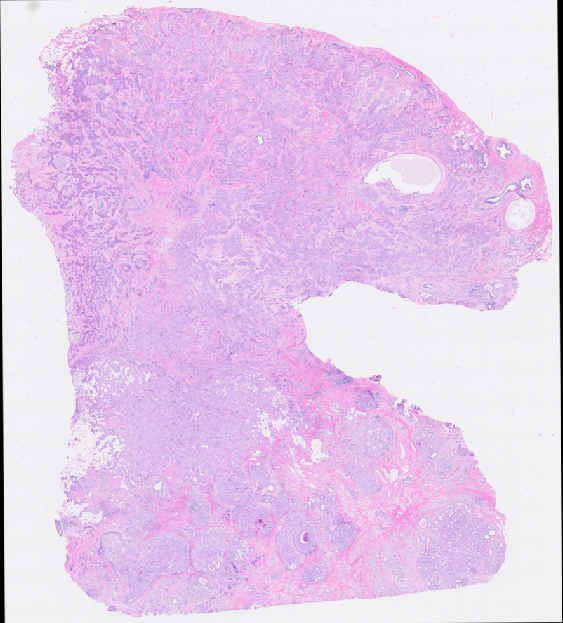

Refer to caption

(a) Raw image

(b) Tumor regions

(c) Immuno regions

(d) Stroma regions

(e) Adiposew regions

(f) Necrosis regions

Figure 3: Results showing the probability heat map of various classification result.

In addition, with the information contained in the ST, users can easily identify different regions within tissue samples. This capability is further enhanced by the functionality provided by QuST, which allows for classification across whole slides. As a result, the combination of QuPath and ST data provides a valuable ground truth for deep learning algorithms to perform tasks such as cell classification and region segmentation. One example is showing in Figure. 3.